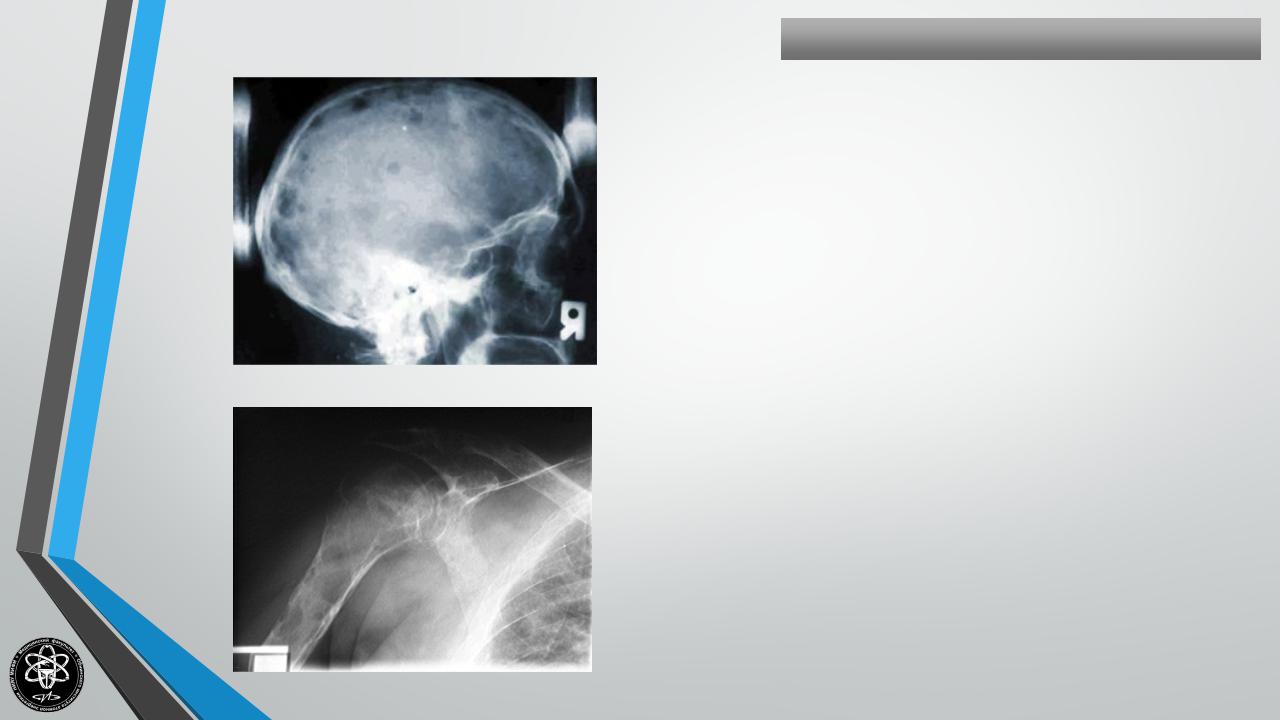

МИЕЛОМА(болезньРустицкого)

Опухоль костного мозга. Поражаемый возраст — пожилой.

Клиника — слабость, боли в конечностях, анемия.

Излюбленная локализация — кости черепа, позвоночник ,грудина, ребра, таз.

Варианты: миэлобластома, миэлоцитома, эритробластома, лимфоцитома, плазмоцитома.

Клиника: боли, припухлость, переломы, неврологические симптомы.

Лабораторные данные: гиперпротеинемия, гипоглобулинемия, белок Бенс-Джонса в моче, анемия, нейропения, лимфоцитоз, нейтрофилез.

Миэломноклеточная метаплазия костного мозга. Уточняет диагноз — стернальная пункция.

На рентгенограммах — кистозные просветления иногда солитарного типа. Лечение паллиативное (сарколизин, стероидные гормоны и пр.).